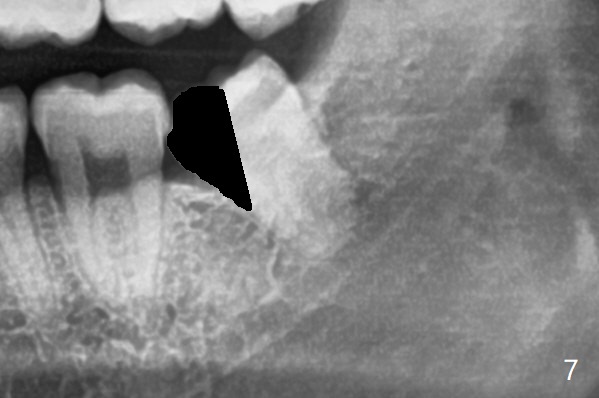

下牙槽神经管(*)位于智齿根尖下方(图一);而没有颊侧沟形成,也没有大量松动智齿,包括牙根,直接切割牙(图六:黑线),去除近中牙齿(图七:黑色)